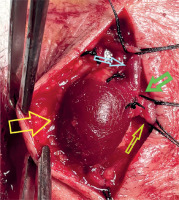

Figure 4

The aneurysm was dissected free from the surrounding subcutaneous tissues. A neck was revealed (green arrow), suggesting the diagnosis of a venous pseudoaneurysm (yellow arrow), which was not confirmed on histopathology. The efferent (light green arrow) and the afferent vein (light blue arrow) were evident